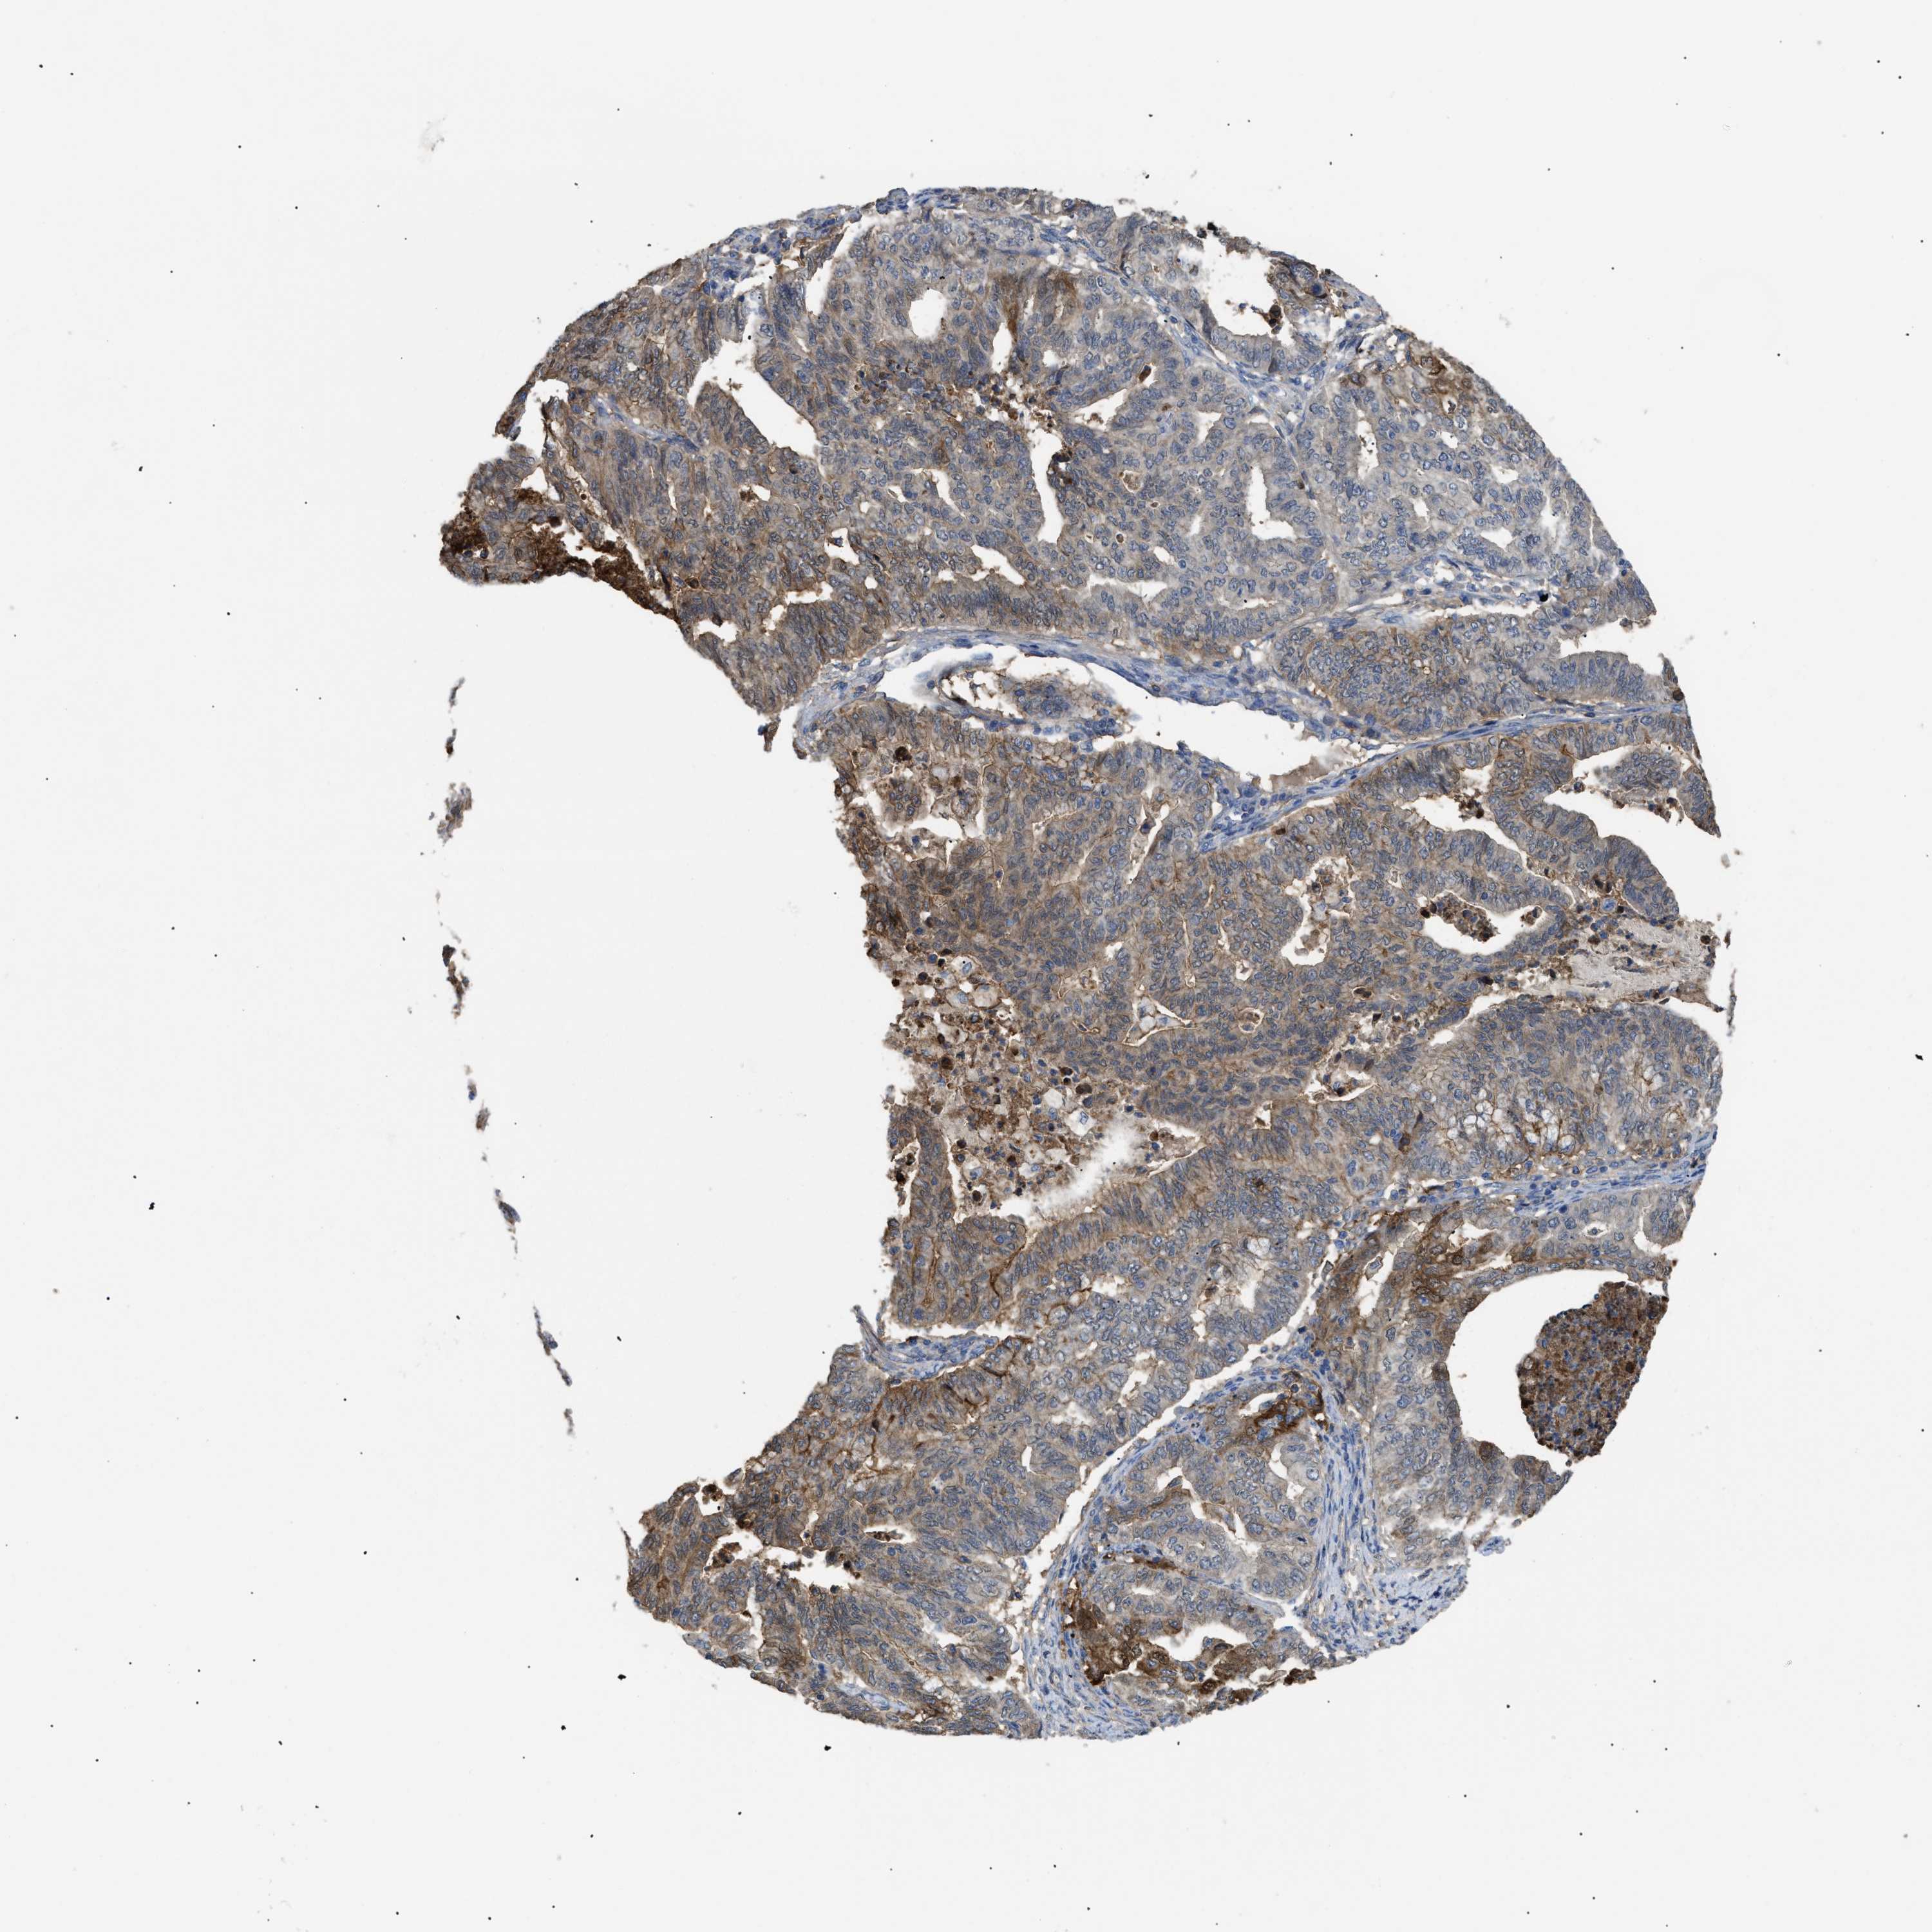

ENDOMETRIAL CANCER - Protein expressioni

A mouse-over function shows sample information and annotation data. Click on an image to view it in a full screen mode. Samples can be filtered based on level of antibody staining by selecting one or several of the following categories: high, medium, low and not detected. The assay and annotation is described here.

Note that samples used for immunohistochemistry by the Human Protein Atlas do not correspond to samples in the TCGA dataset.

Antibody stainingi

Antibody staining in the annotated cell types in the current human tissue is reported as not detected, low, medium, or high, based on conventional immunohistochemistry profiling in selected tissues. This score is based on the combination of the staining intensity and fraction of stained cells.

Each image is clickable and will lead to virtual microscopy that enables deeper exploration of all samples and also displays staining intensity scores, fraction scores and subcellular localization as well as patient and tissue information for each sample.

Antibody HPA007393

Antibody CAB005076

Antibody CAB017560